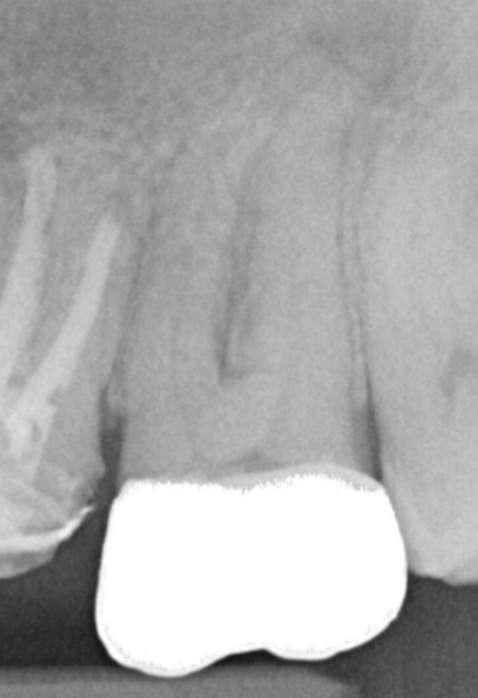

Röntgenologischer Befund: Therapie

Das präoperativ angefertigte diagnostische Röntgenbild zeigt eine insuffiziente Amalgamfüllung im distalen Approximalraum. Die mesiale Wurzel weist eine periapikale Osteolyse auf (Abbildung 1).

Abbildung 1: Präoperative Diagnostische Aufnahme